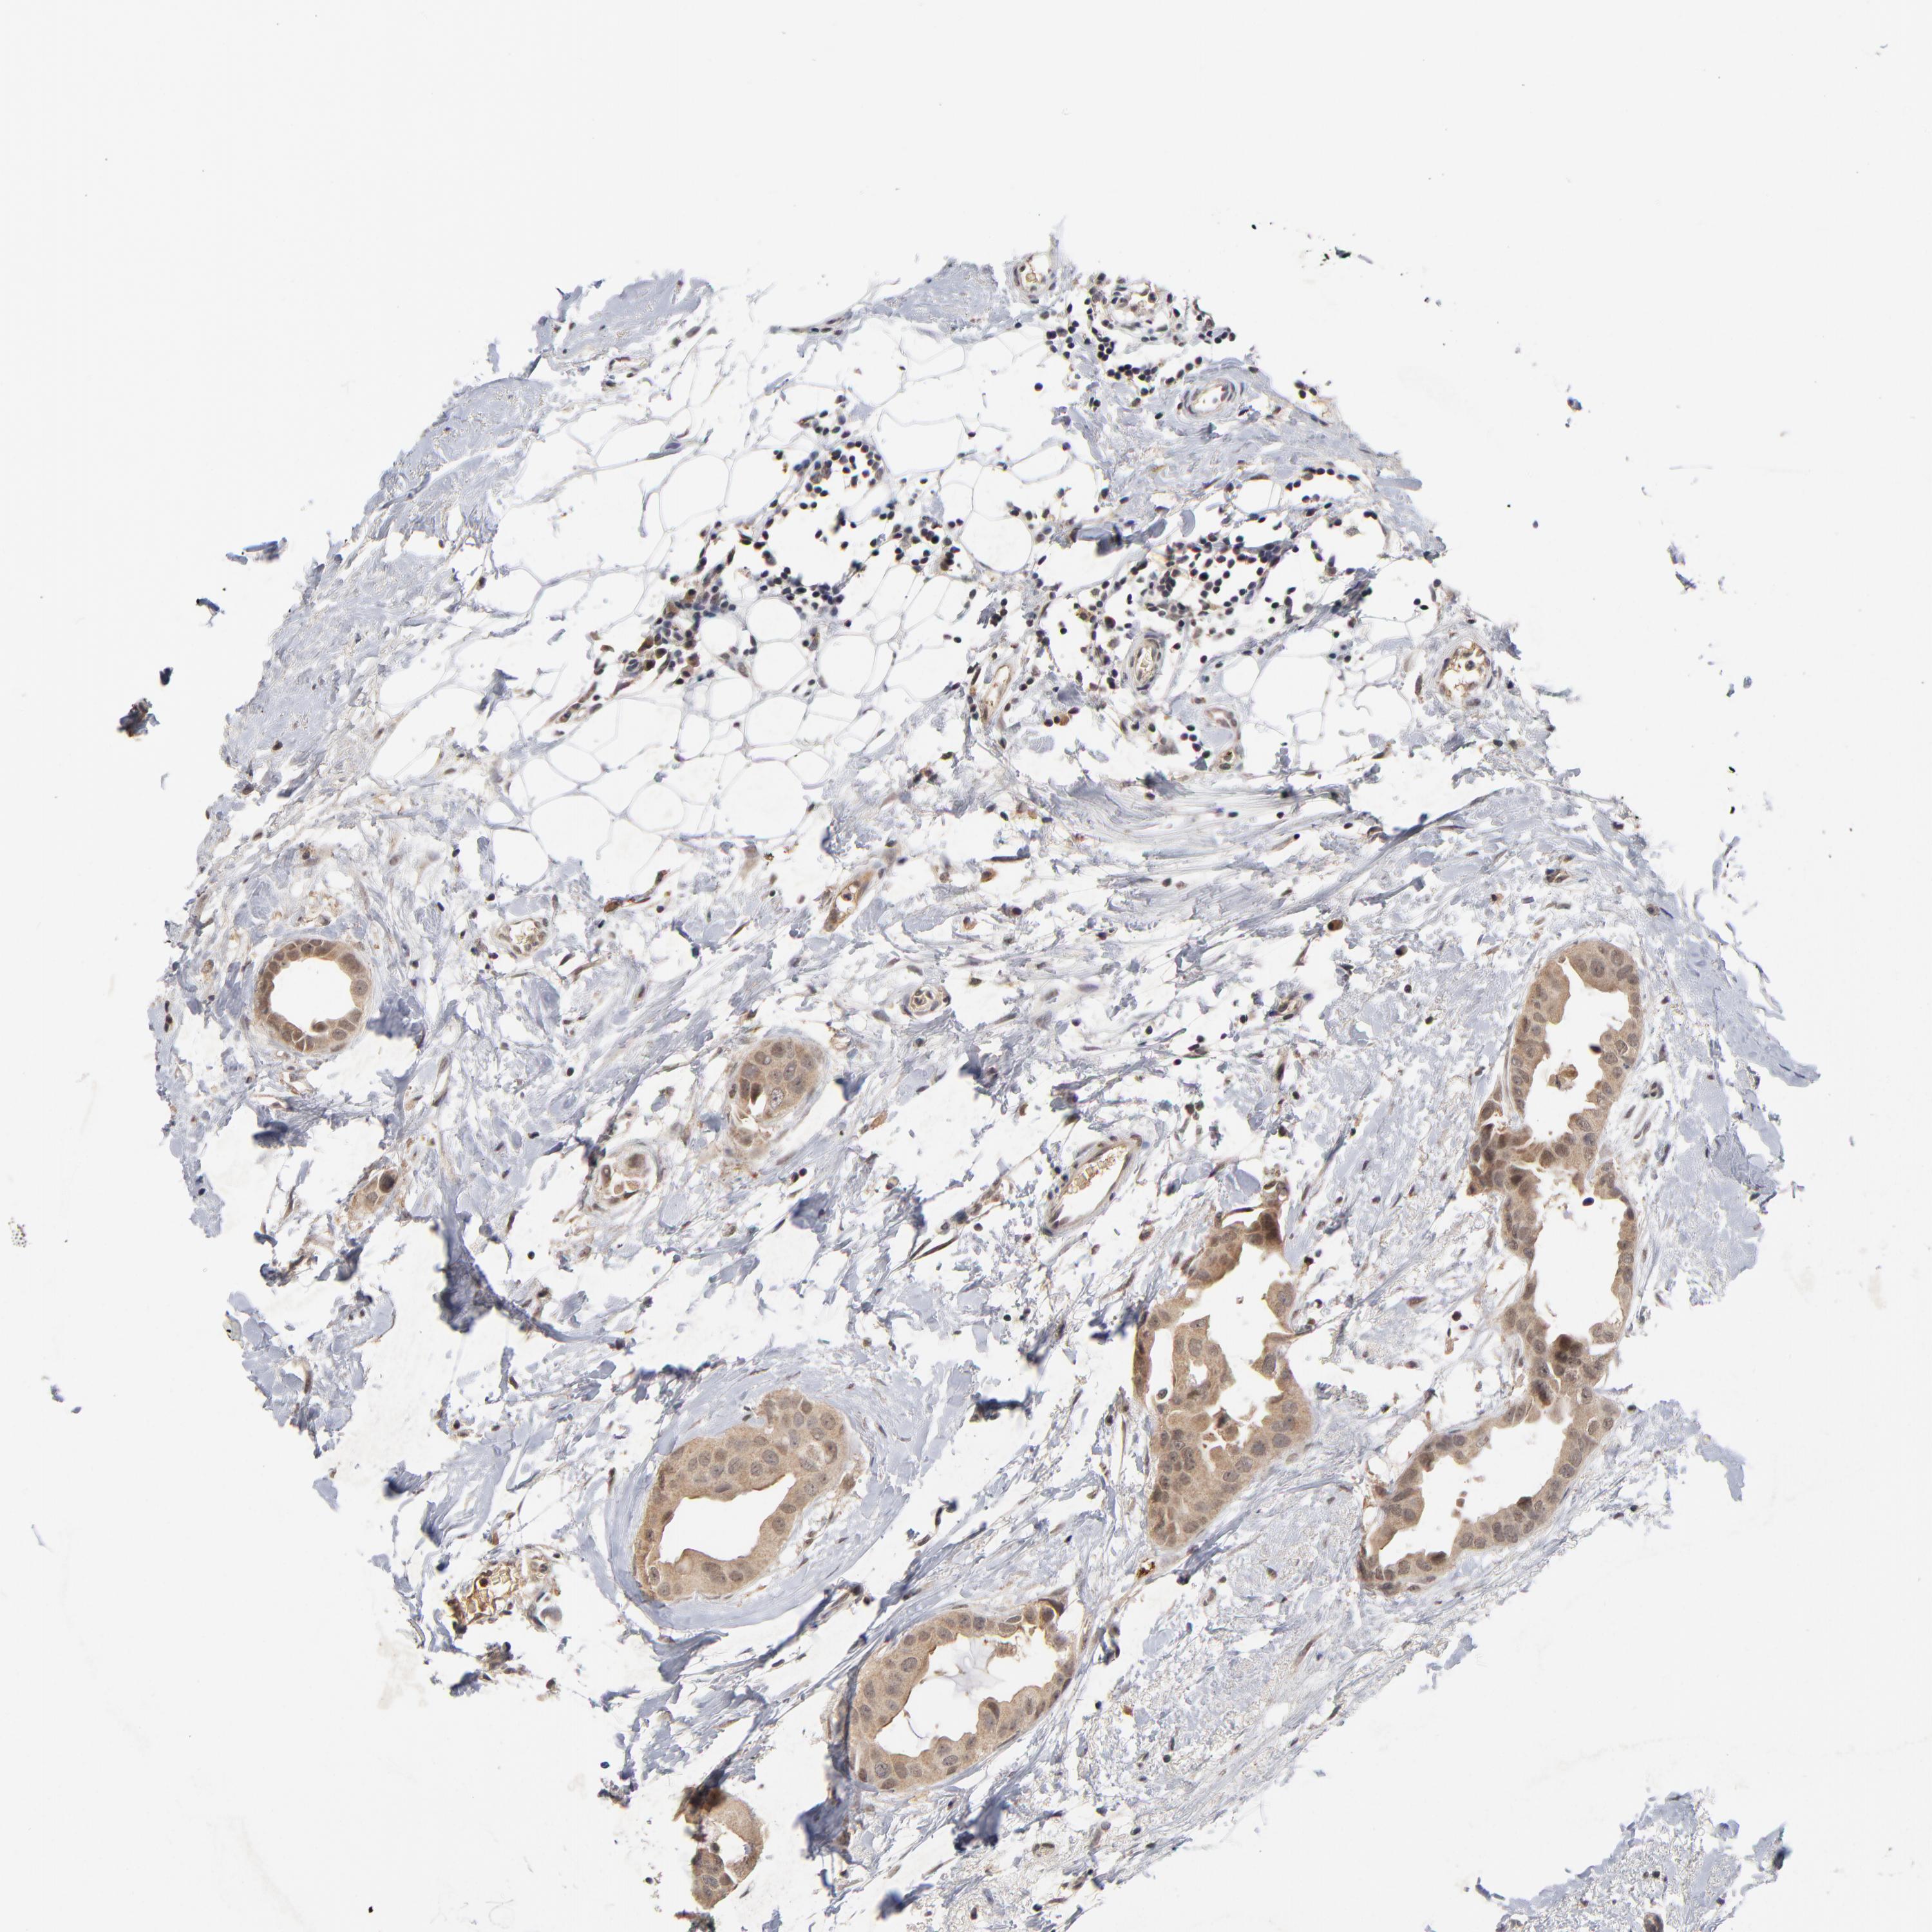

CANCER BREAST CANCER Show tissue menu

BRCA TCGA BRCA VALIDATION PROTEIN EXPRESSION